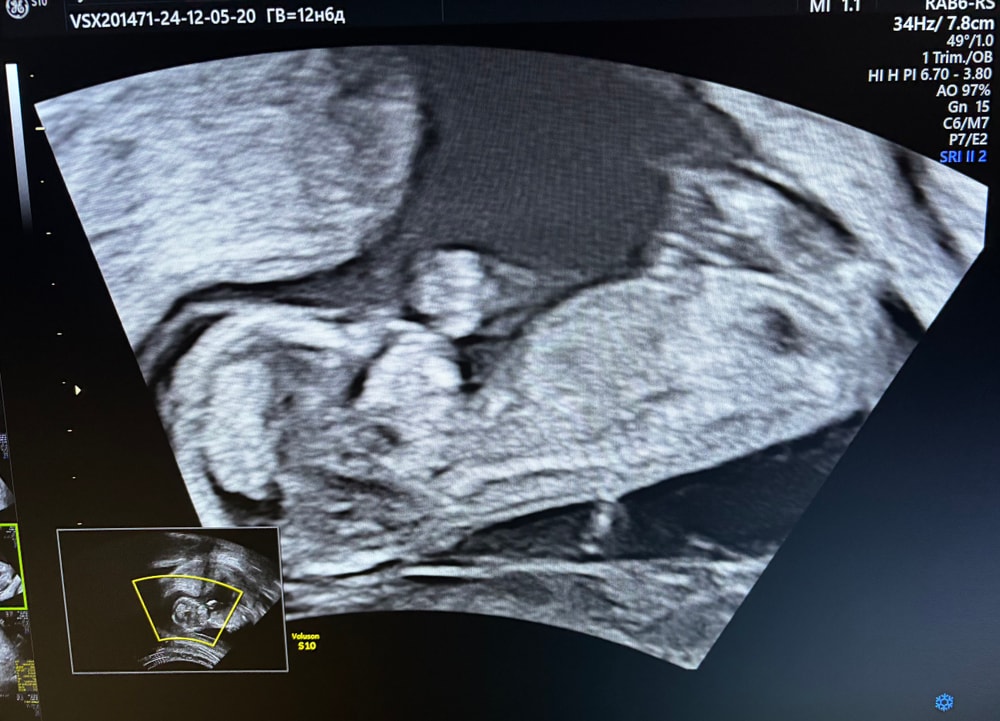

13,5 по узи. А что вы рассматриваете? Пол?) От положения ребенка же в момент узи зависит, вообще многое видно уже.. наше пятками сверкало и за голову обеими руками хваталось 😂 видео разрешили снимать, в движении все лучше видно. Изображение Изображение